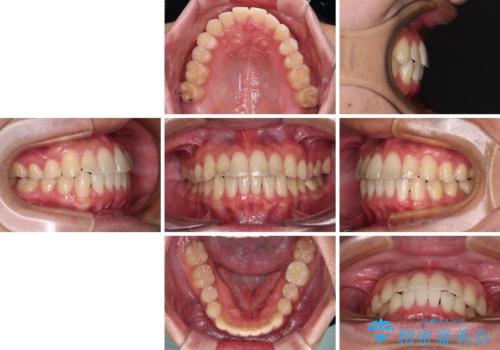

【モニター】前歯のクロスバイトと隙間を改善 インビザラインによる矯正治療

- 前歯のクロスバイトを気にして来院された患者様です。

骨格的には問題がなかったため、インビザラインを用いて咬み合わせを改善していくこととしました。

インビザライン特有の、奥歯の咬み合わせの問題もなく、しっかりと歯列を改善することができました。

舌側転位している上顎側切歯(内側に引っ込んでいる真ん中から2番目の歯)は、インビザラインが最も移動を苦手とする歯であり、これ以上の改善を望まれる場合にはワイヤー矯正、あるいはワイヤー矯正の併用をお勧めいたします。